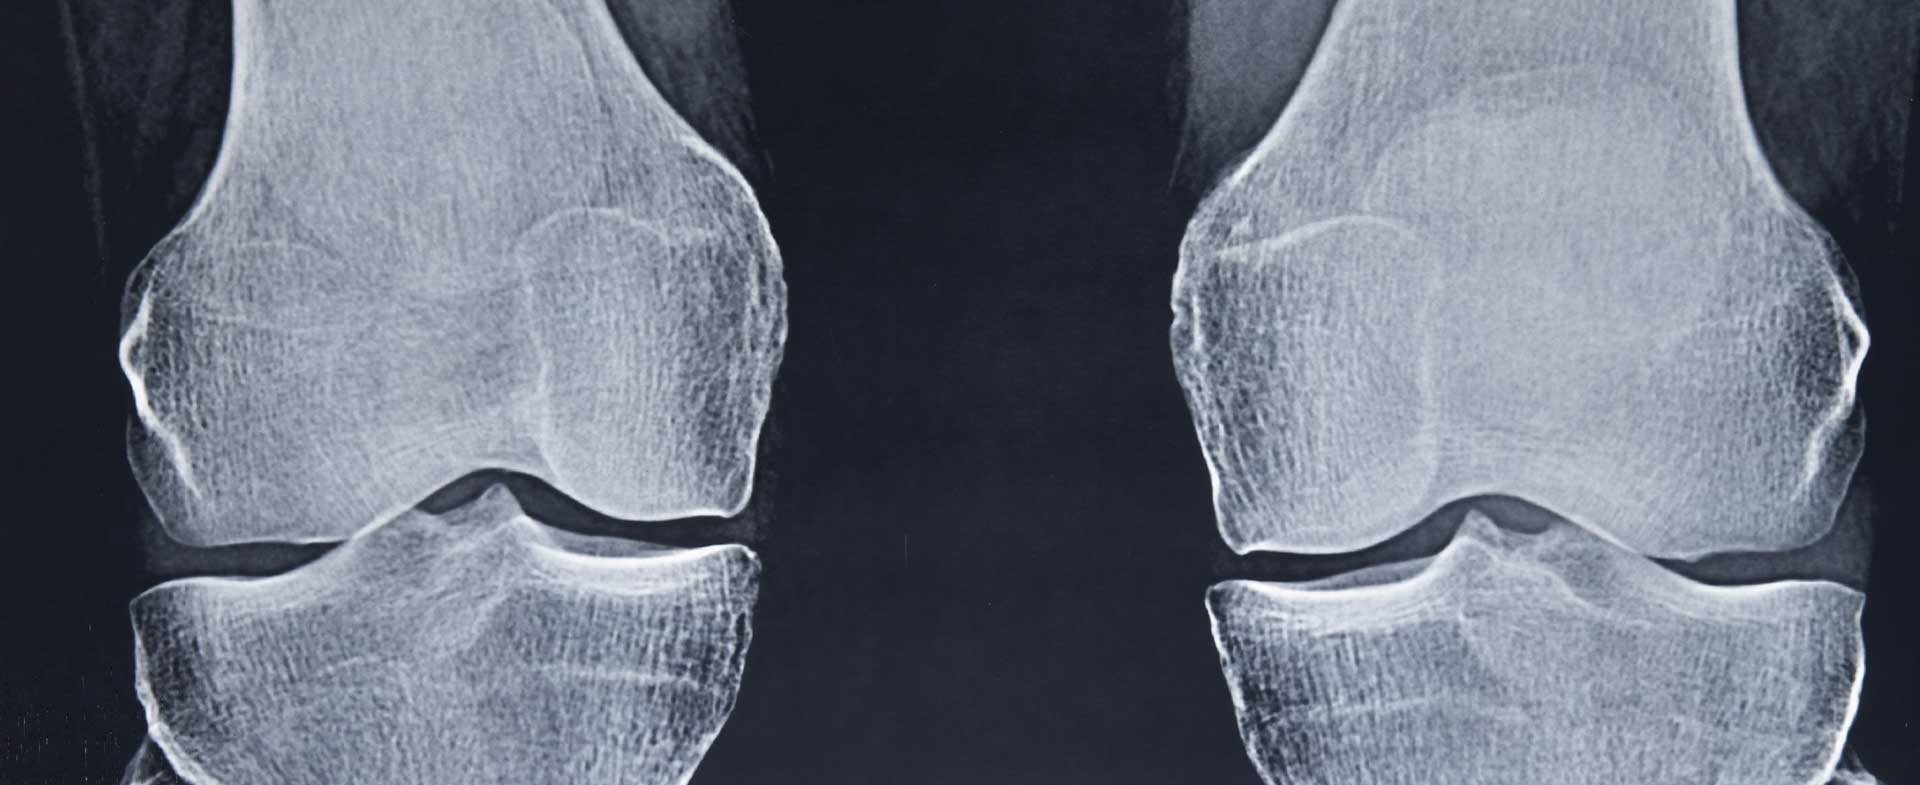

Osteoarthritis – a degenerative joint disease – can be challenging to live with. It causes pain and stiffness, making it difficult to go about your daily life. Virtually no one is immune to it as they get older, since it’s caused by cartilage wearing down over the years, says Ramsey Shehab, M.D., a sports medicine physician at Henry Ford Health.

“Age is the greatest risk factor for osteoarthritis, but genetics and getting injured at a young age can also play into when someone will develop osteoarthritis – and how severe it will be,” says Dr. Shehab.